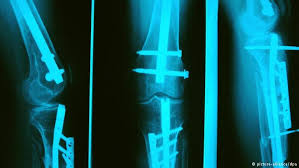

كبار السن أكثر عرضة للسقوط والإصابة بكسور العظام، لكن التدخل الجراحي المعتاد ليس هو الحل الأفضل، لما للجراحات الكبيرة من مضاعفات قد لا يتحملها المسن. وتساهم تقنية "الضوء الأزرق" في حل هذه المشكلة لدى كبار السن أو حتى مرضى هشاشة العظام، إذ تساعد هذه الطريقة في حل مشكلة من لا يتحمل عمليات زراعة العظام التقليدية.

ويعتمد استخدام تلك التقنية على عمل قسطرة من خلال فتحة صغيرة يمكن من خلالها الوصول لمكان الكسر دون الحاجة لعمل فتحة كبيرة. ويمكن للطبيب هنا زراعة قطعة صناعية في العظام وتثبيتها. وهنا يعمل الضوء الأزرق على صلابة القطعة الصناعية المزروعة وتثبيتها مكان الكسر. وفي النهاية يستطيع المريض التخلص من آلام الكسر سريعا ولا يبقى من أثر العملية سوى بعض الآثار لفتحات صغيرة على الجلد